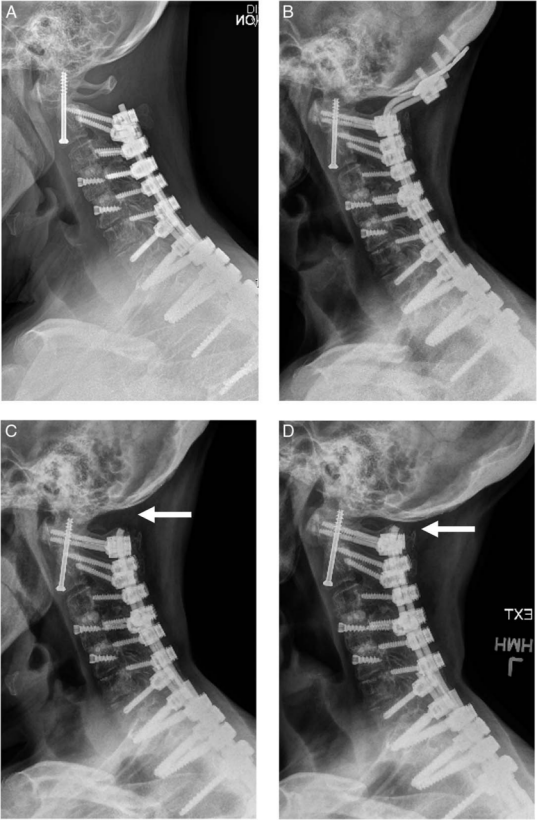

图 4 (A)一名 64 岁女性,齿状突骨折经前路齿状突螺钉固定术后不愈合的颈椎侧位 X 线片;(B)因颈胸段融合范围较广,采用后路 C1/2 融合联合枕骨束缚(不融合枕骨)固定;枕骨束缚术后 14 个月 X 线片显示(C)屈曲位和(D)伸展位,移除枕骨板后,枕骨 - C1 节段恢复 23° 活动度(箭头所示)。